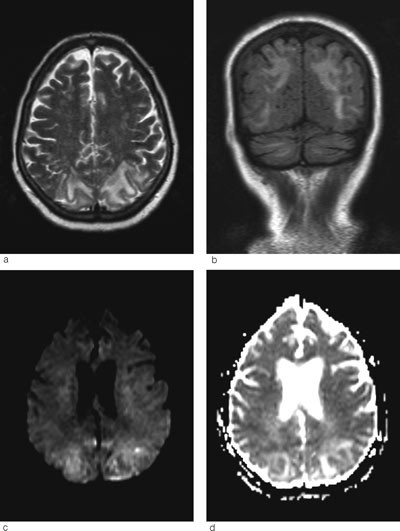

Senere samme dag ble det gjort MR-undersøkelse. Denne viste vasogent ødem parietooksipitalt, cerebellart og delvis i hjernestammen (fig 1a-d). Det var ingen tegn til infarkt eller sinusvenetrombose. Funnene var best forenlig med posterior reversibel encefalopati-syndrom (PRES). Pasienten ble overflyttet nevrologisk avdeling for videre behandling.

Ved MR cerebrum er det som regel karakteristiske funn ved posterior reversibel encefalopati-syndrom med vasogent ødem parietooksipitalt bilateralt (5). I uttalte tilfeller, som hos vår pasient, kan man se slike forandringer i hjernestammen og cerebellum, sjeldnere i fremre deler av cerebrum (6). T2-vektede MR-bilder og FLAIR-sekvenser er sensitive for ødem, som vises som høysignalforandringer (fig 1a-b).

Hjerneødem kan være cytotoksisk (cellulært) eller vasogent (interstitielt). Ofte foreligger det en kombinasjon. Ved hjerneinfarkt dominerer det cytotoksiske ødemet og celledød (fig 3a-b). Ved posterior reversibel encefalopati-syndrom får man et vasogent ødem som i utgangspunktet er reversibelt, men som uten behandling kan utvikles til cytotoksisk ødem og gi permanent cellulær skade. Ved hjelp av MR med diffusjonsvekting (DWI) og ADC-kart kan man skille mellom cytotoksisk og vasogent ødem. Ved MR med diffusjonsvekting er det høyt signal ved cytotoksisk ødem, mens det vanligvis er lavt signal eller ingen signalendringer ved vasogent ødem. I noen tilfeller får man likevel høyt signal ved posterior reversibel encefalopati-syndrom. Dette skyldes at DWI-resultatet er satt sammen av bidrag fra både T2-vekting og diffusjonsvekting. Høyt signal på T2 kan derfor skinne igjennom til diffusjonsbildet. Dette var også tilfellet hos vår pasient (fig 1c). Det er derfor viktig med ADC-kart, hvor bidraget fra T2 er fjernet og man får et rent diffusjonsbilde (7). ADC-kart viser alltid lavt signal ved cytotoksisk ødem og høyt signal ved vasogent ødem, som ved posterior reversibel encefalopati-syndrom (fig 1d).